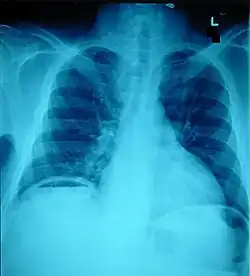

Ten percent of people with polytrauma who had no signs of abdominal injury did have evidence of such injuries using radiological imaging.[1] Diagnostic techniques used include CT scanning, ultrasound,[1] and X-ray.[7] X-ray can help determine the path of a penetrating object and locate any foreign matter left in the wound, but may not be helpful in blunt trauma.[7] Diagnostic laparoscopy or exploratory laparotomy may also be performed if other diagnostic methods do not yield conclusive results.[5]